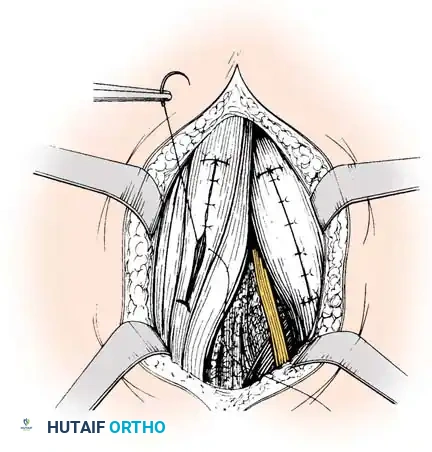

Lateral Hamstring Lengthening (If Indicated):

* If further correction is required to achieve full extension, proceed to the lateral side.

* Identify the biceps femoris tendon.

* Crucial Step: Meticulously isolate the biceps femoris from the common peroneal nerve, which lies immediately along its medial and posterior border.

* Pass a blunt right-angle instrument deep to the biceps femoris tendon to protect the nerve. Incise its tendinous portion transversely at two levels approximately 3 cm apart, leaving the muscle fibers intact.

Incisions in biceps femoris; note hemostat anterior to peroneal nerve protecting the neurovascular structures.

Closure:

* Perform a similar dynamic lengthening maneuver by flexing the hip and extending the knee to ensure the lateral structures slide appropriately.

* Close all individual tendon sheaths meticulously with absorbable suture.

* Do not close the deep fascia. Leaving the deep fascia open prevents postoperative compartment syndrome and allows for the expanded volume of the sliding muscle bellies.

Separate meticulous closure of each tendon sheath; deep fascia is not sutured.